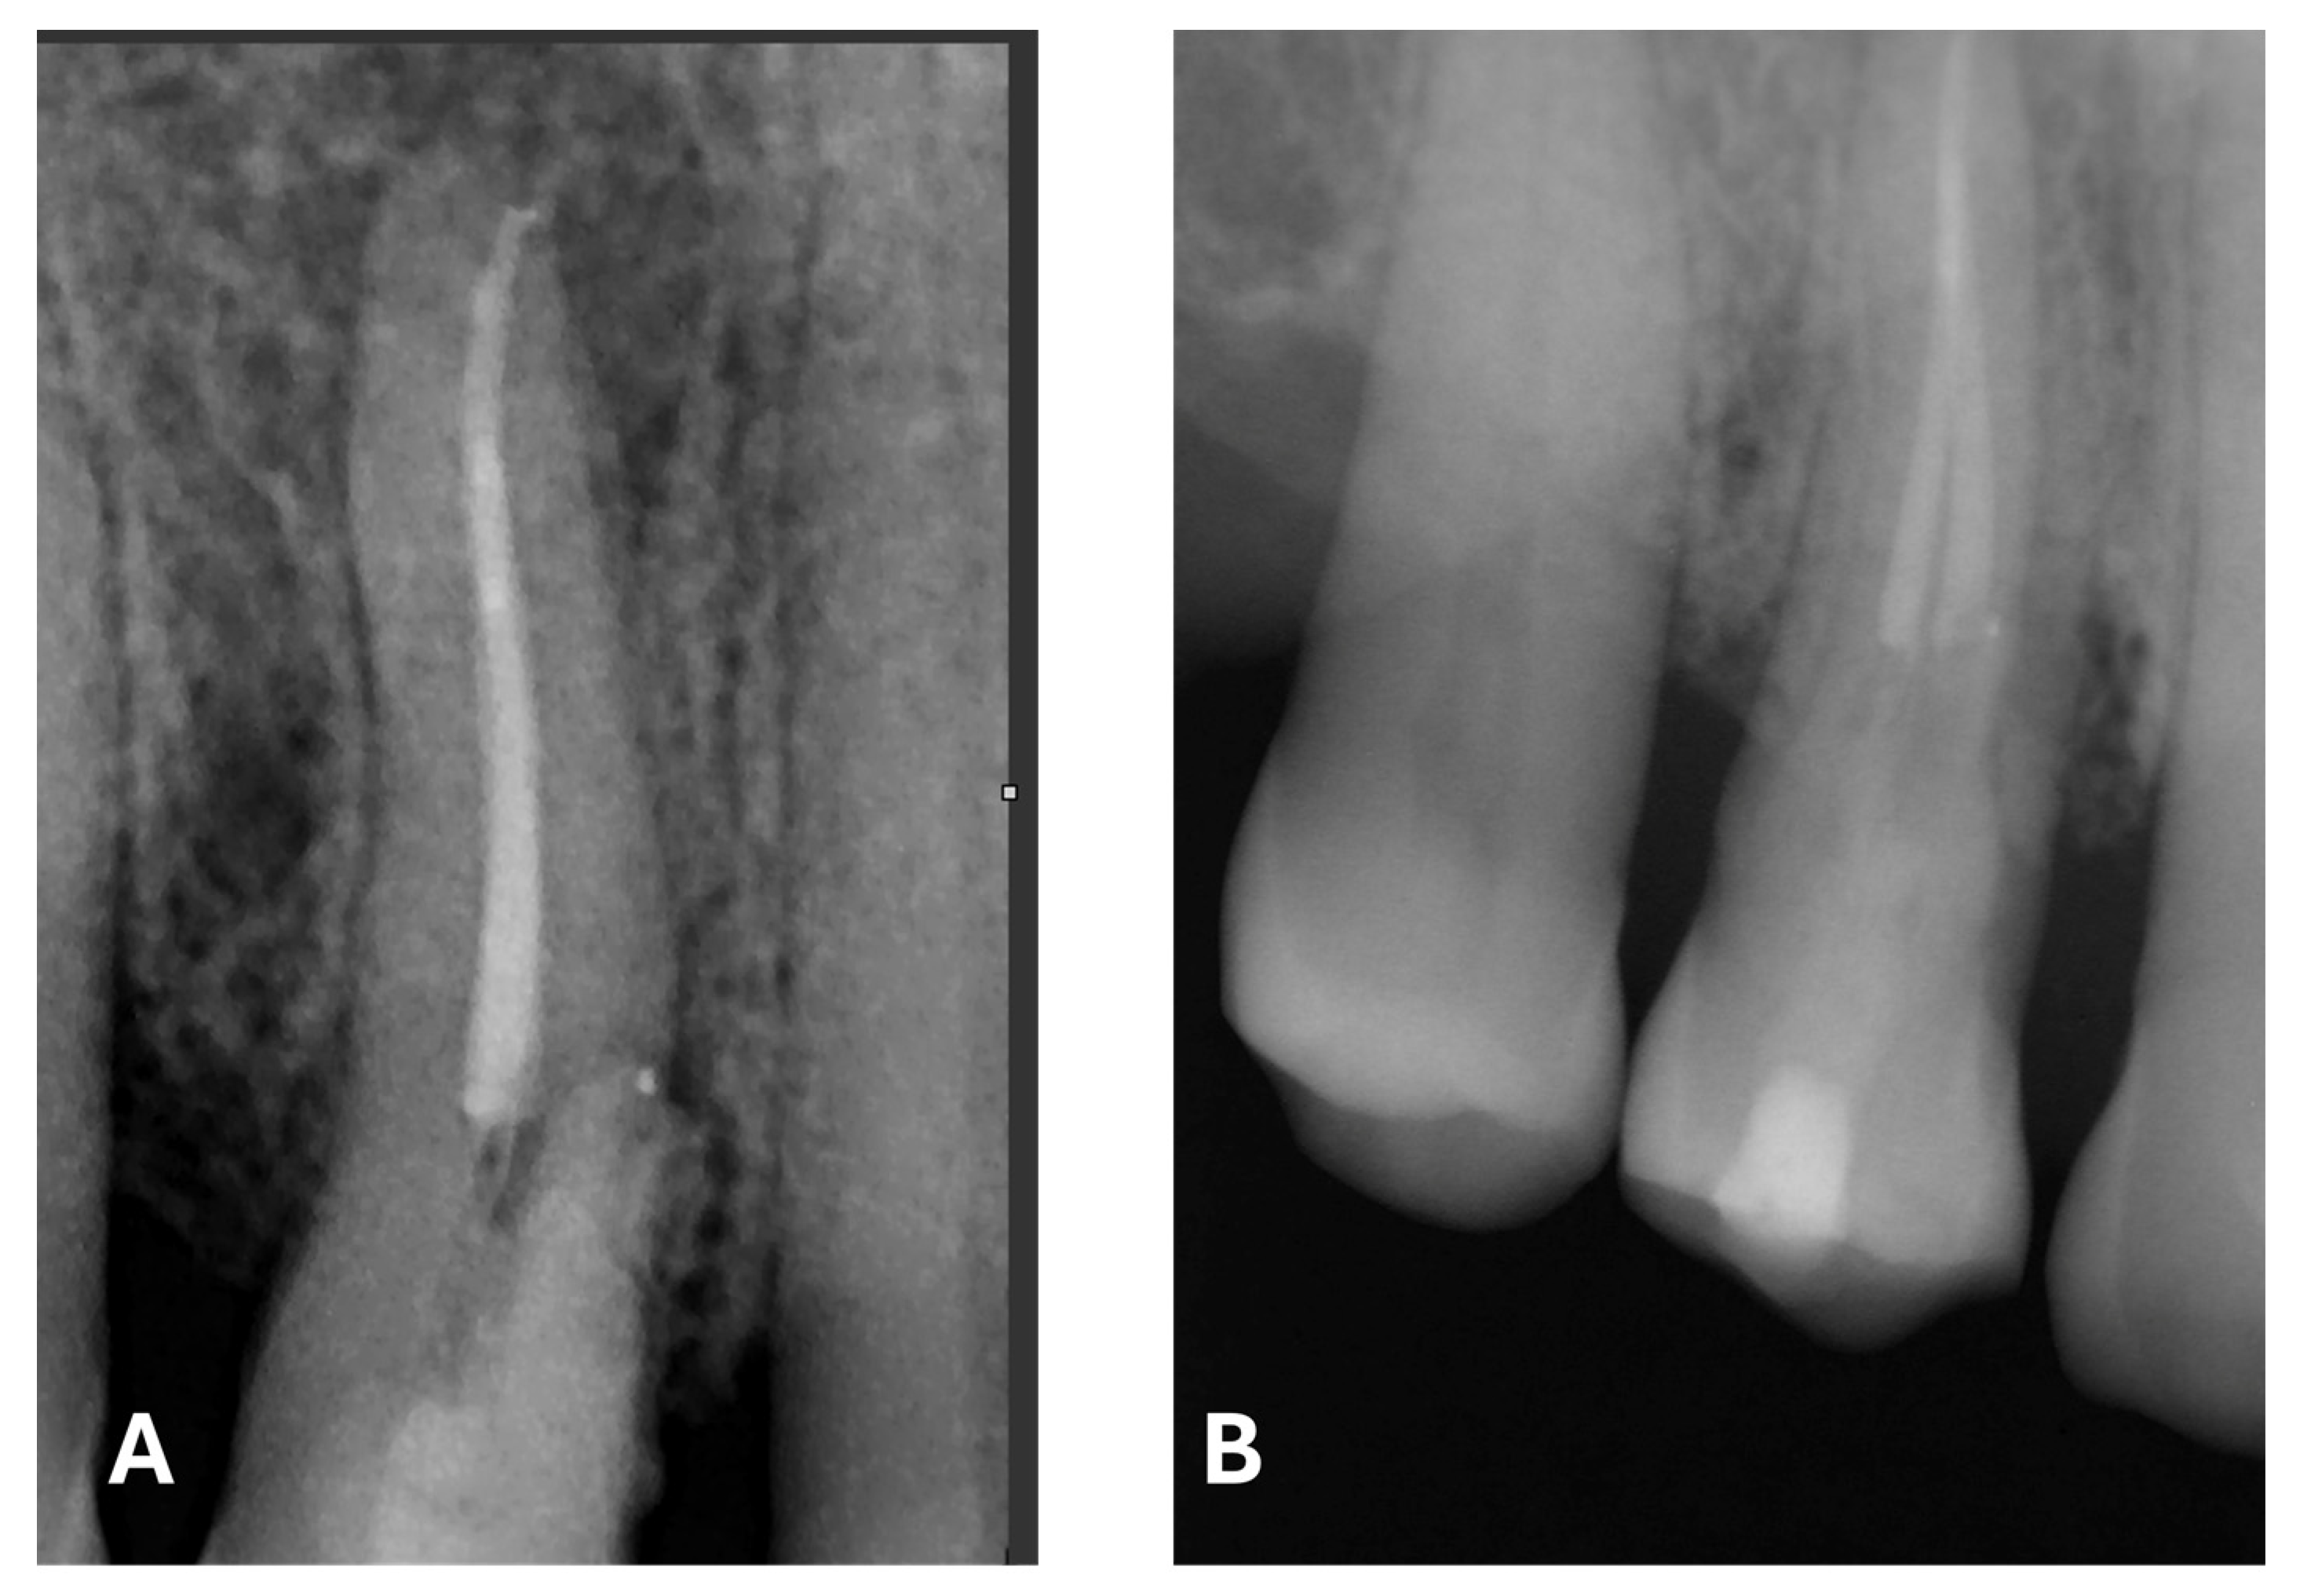

Post-treatment radiograph with composite filling. (A) focus on the periapical lesion, root canal obturation and Biodentine application. (B) focus on composite filling. Note the radiographic evidence of widening of the lamina dura in the mesiocervical region.

The radiographic quality of endodontic treatment—particularly in regard to canal filling density, appropriate taper, and respect for the working length—is significantly associated with a lower incidence of endodontic failure. Inadequate fillings, overextensions, underfillings, or the presence of voids within the canal have been correlated with a higher likelihood of persistent periapical lesions and a reduced treatment success rate [25].

At the 12-month radiographic follow-up, healing of the EPL was confirmed. Restoration of the lamina dura and the periodontal ligament adjacent to the treated site was observed (Figure 16 and Figure 17).

Figure 16.

Intraoral radiography of tooth 1.4 at 12-month follow-up.

Figure 17.

EPL before (A) and after treatment (red circle showing mesiocervical widening of the lamina dura space) (B) and at 12-month follow-up (C) with radiographic evidence of restoration of the lamina dura (green circle), periodontal ligament space and absence of PL.